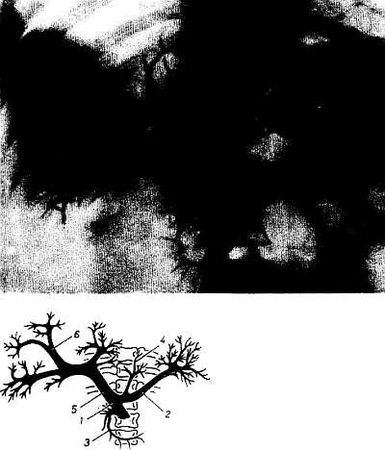

Удается получить рентгеновское изображение вен конечностей и внутриорганных вен. Путем введения рентгеноконтрастного вещества через пупочную вену можно получить изображение воротной вены и ее ветвей внутри печени (портография; рис. 252). При этом на рентгенограмме выявляются тончайшие вены, вследствие чего такая рентгенограмма венозных разветвлений на живом не уступает коррозионному препарату печени.

Рис. 252. Сосудистый рисунок печени и селезенки, а также всей портальной системы. Рентгенограмма.

1 - v. mesenierica superior; 2 - v. lienalis; 3 - v. pancreaticoduodenalis; 4 - v. gastrica sinistra; 5 - v. portae; 6 - внутрипеченочные вены.